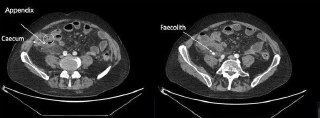

Британські хірурги видалили 70-річному чоловіку подвійний апендикс Британські хірурги розповіли про рідкісний випадок:...